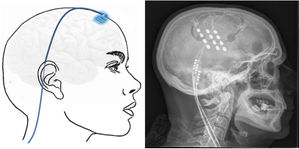

Técnica: la cirugía se realiza en pacientes seleccionados con criterios estrictos161 y se inicia mediante la colocación de un marco de estereotaxia y, posteriormente, se realiza una TC craneal, donde se ubican marcas de estereotaxia que localizan el hipotálamo. A continuación, se fusionan las imágenes obtenidas con la TC craneal con la RM cerebral realizada previamente en neuronavegador, obteniendo el mejor punto de entrada y trayecto para dirigir el electrodo a la diana. El electrodo se inserta en la diana a través de un orificio frontal de trepanación (fig. 7) y se tuneliza subcutáneamente el cableado desde el orificio de trepanación hasta el área paraumbilical o infraclavicular, donde se coloca el generador.

Esquema mostrando el electrodo implantado en el hipotálamo (flecha azul discontinua) a través de un orificio de trepanación frontal y cableado subcutáneo. A la derecha TC craneal post-cirugía que muestra el electrodo implantado en el hipotálamo en un paciente con cefalea en racimos crónica refractaria izquierda.